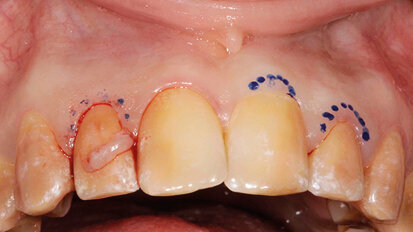

Trattamento estetico-funzionale in un caso di amelogenesi imperfetta generalizzata

Una paziente affetta da amelogenesi imperfetta generalizzata (Figg. 1a, 1b) aveva richiesto in età adulta un trattamento estetico. La paziente ...